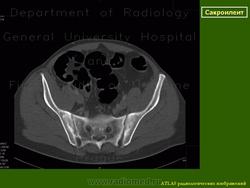

КТ КПС в корональной (а) и аксиальной (b) проекциях: двусторонний сакроилиит III стадии. http://congress-ph.ru/common/htdocs/upload/fm/rar/17/prez/A-10-02.pdf